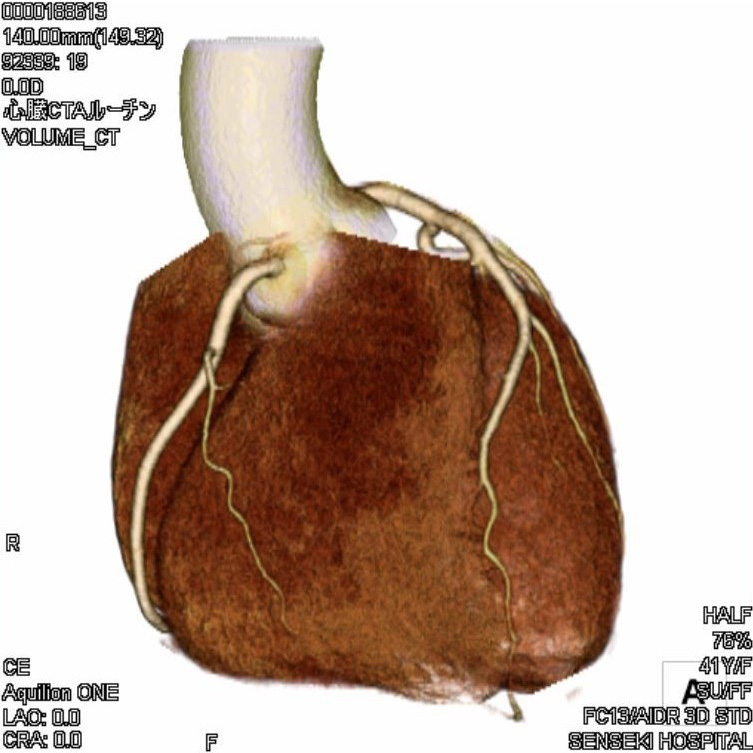

CT室:Aquilion ONE (Canon)・Revolution EVO (GE)

CTとは、X線という放射線を使用して人体の輪切り画像を撮る装置です。その画像を使用して、さまざまな方向の断面像や3Dの画像を再構成をすることもあります。

当院には320列と64列のCTがあります。

■320列CT (Aquilion One)

頭と心臓の検査